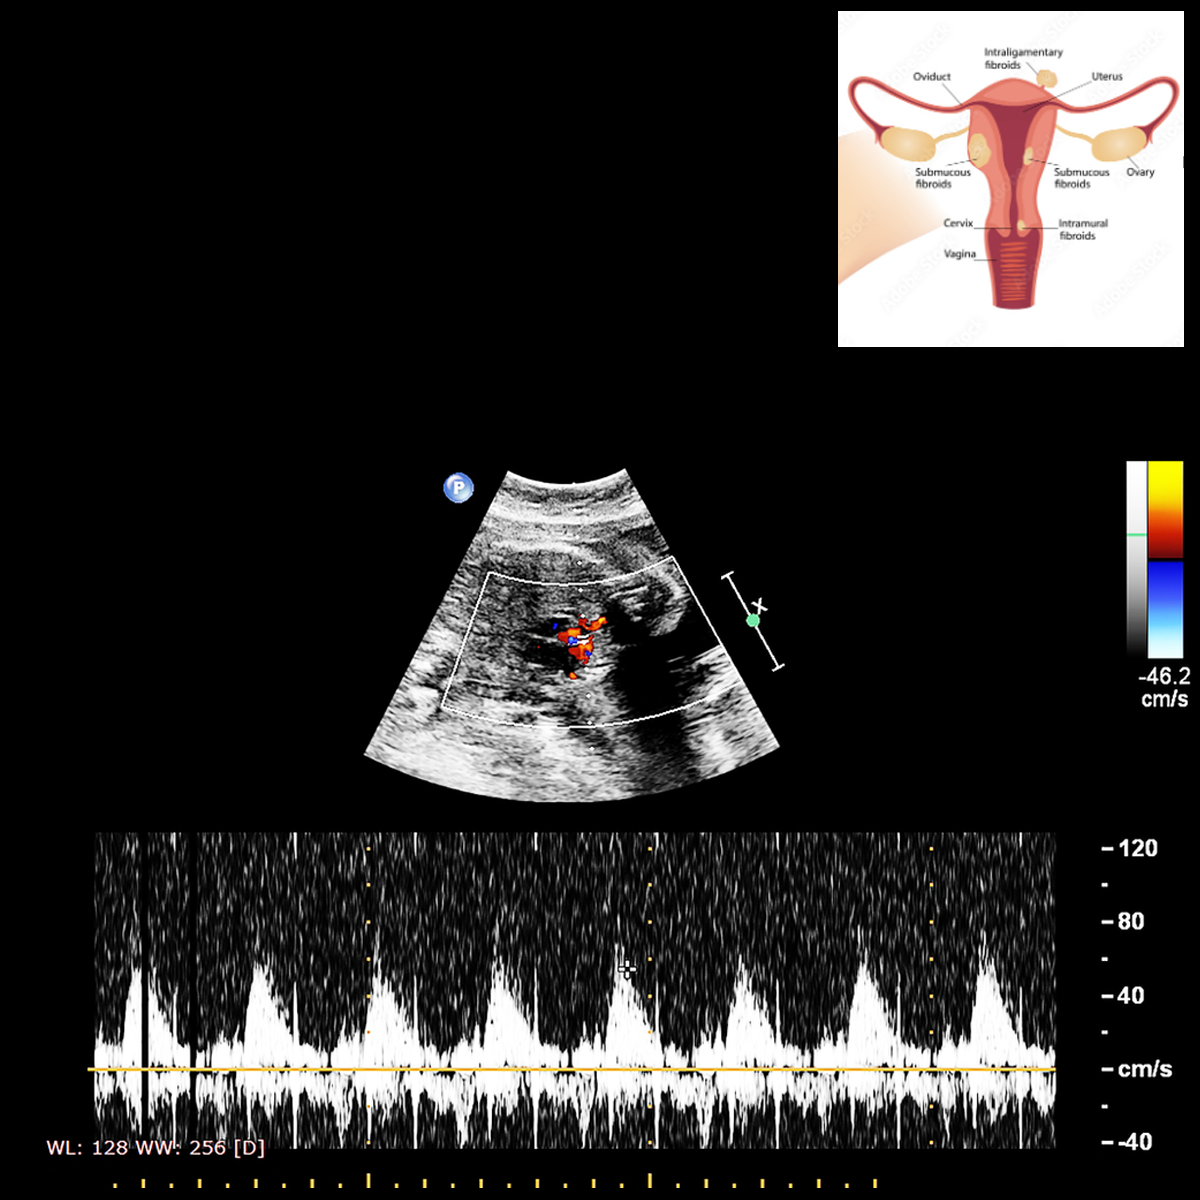

VII. Transvaginal Scan For Cervical Screening And Pre-eclampsia Screening (From 12 weeks):

This ultrasound is performed transvaginally at 20-24 weeks to look for cervical length and maternal uterine artery blood flow. It helps in screening women who are at increased risk for preterm delivery and hypertensive disorders.